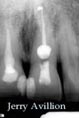

The invited case # 15 : Dr. Jerry Avillion

Our fifteenth guest is Dr. Jerry Avillion. Dr. Avillion is B.S. in Biology, Penn State University 1980. His D.D.S. is from the Medical College of Virginia, 1984, and his Certificate in Endodontics is also from the Medical College of Virginia, 1986. He actually has a private practice dedicated to Endodontics in Fort Smith, Arkansas.

Here you can enjoy several "supreme" cases performed by Dr. Avillion :

(click on the images to enlarge)